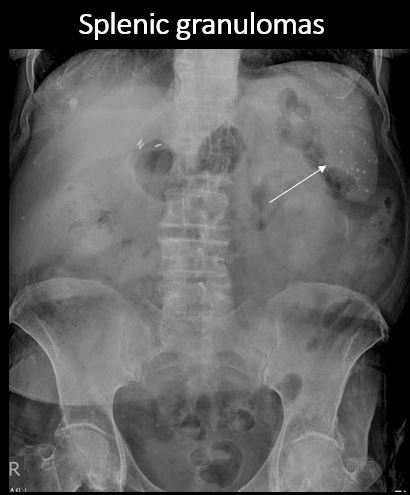

There are splenic associated calcifications. |

yes | NA |